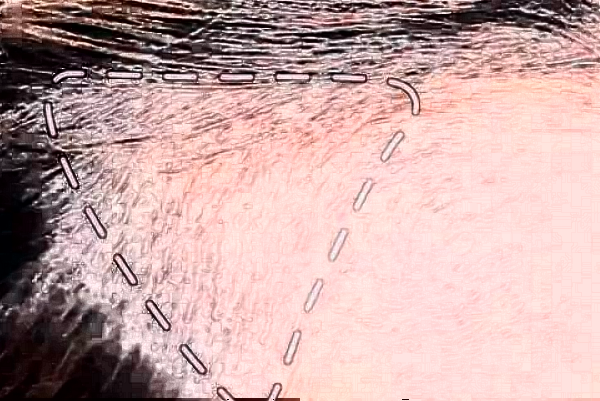

自己的發(fā)際線頭發(fā)稀少,一直以劉海來遮擋,看到別人梳著高馬尾,自己很是羨慕不已,所以在朋友的支持下來到了阜陽市人民醫(yī)院做植發(fā)極限手術(shù)的項目,在醫(yī)生診斷之后說自己可以進行此種手術(shù)的方法,從早上10點開始醫(yī)生會先設(shè)計發(fā)際線的形狀,然后對自己進行抽血化驗,開始剃發(fā)做準備,雖然說手術(shù)過程比較漫長,但是醫(yī)生和護士都是很認真的為自己做手術(shù),醫(yī)生的技術(shù)也比較嫻熟,就是打麻藥的時候有一些輕微的疼痛,整體手術(shù)操作沒有感覺到疼痛的現(xiàn)象,手術(shù)操作之后,醫(yī)生囑咐建議做好術(shù)后的護理工作,大概在兩個月之后發(fā)際線長出了新頭發(fā),看到自己密密麻麻的頭發(fā),心情變好了,終于可以告別劉海了。